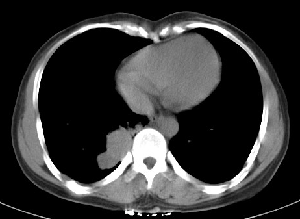

下叶后基底段近膈面见一椭圆形密度均匀增高的阴影,边界较清,其长轴指向内后方,考虑肺隔离症,建议增强扫描了解与主a联系!

三无产品!只能依影论影 :首先考虑炎症,建议抗炎治疗后复查

肺血管畸形也有可能。

1.后纵隔神经原肿瘤,2.炎性假瘤。建议密切结合临床或抗炎治疗后复查。